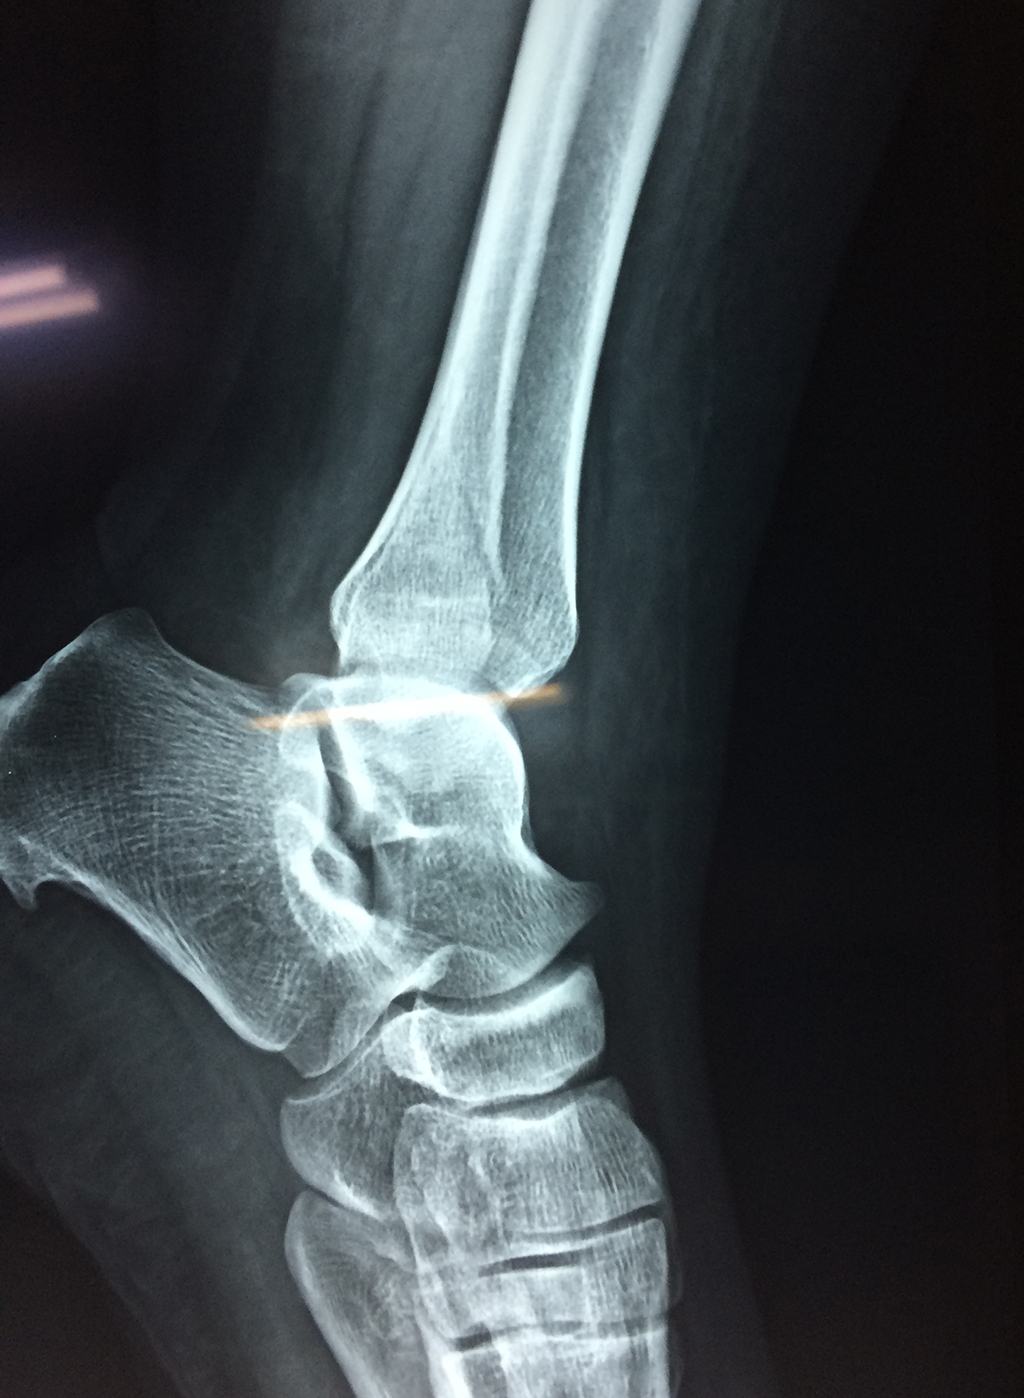

Una fractura de tobillo es la rotura de uno o más de los huesos del tobillo. Estas fracturas pueden ser:

- Parciales (el hueso está sólo parcialmente fisurado, no del todo).

- Completas (el hueso está perforado y está en 2 partes).

- Producirse en uno o ambos lados del tobillo.

Algunas fracturas de tobillo pueden requerir cirugía si:

- Los extremos de los huesos están desalineados entre sí (desplazados).

- La fractura se extiende hasta la articulación del tobillo (fractura intra-articular).

- Los tendones o ligamentos (tejidos que sujetan los músculos y los huesos entre sí) están rotos.

Cuando se necesita cirugía, es probable que esta implique el uso de clavijas de metal, tornillos o placas para sostener los huesos en su lugar mientras la fractura se consolida. Los elementos de soporte pueden ser temporales o permanentes.